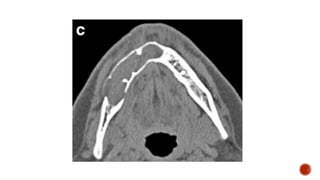

 AP and lateral radiographs of the skull show a well defined lytic lesion involving

the left ramus of the mandible causing scalloping of the medial margin with

associated soft tissue swelling.

MANDIBLE XRAY

 Axiolateral oblique

 The patient is seated upright

 Give true lateral position

 Slightly extend the neck

 Tilt the head towards the detector

 Central ray 25-30 degree cephalad

 The patient is stationary, while the x ray source and the film rotates.

 sitting/standing completely upright

 head immobilized and on a chin rest

 biting down on a radiolucent bite block

 tongue against the hard palate